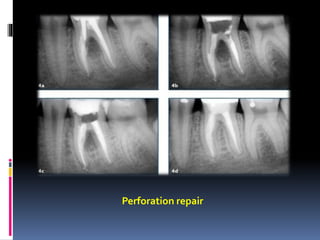

Perforation repair in roots

or furcation

Perforation repair

Perforation repair inroots or furcation